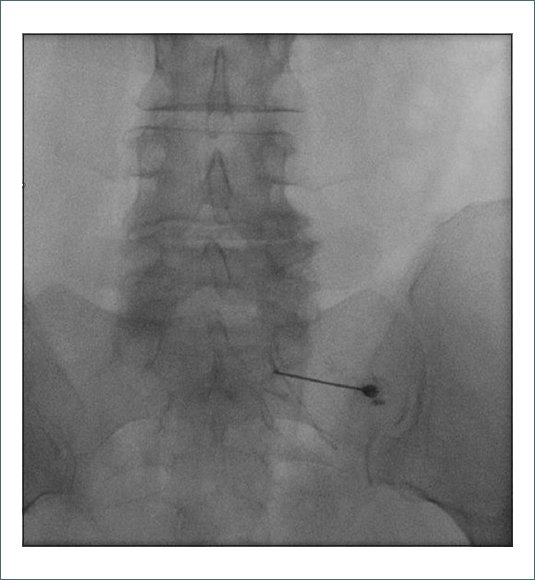

Se realizaron diferentes pruebas complementarias. El electromiograma era compatible con una radiculopatía crónica S1 derecha con discreta pérdida axonal motora. En la resonancia magnética (RMN) lumbar se objetivó protrusión y pinzamiento discal L5-S1, cambios hipertróficos facetarios degenerativos de L3 a S1 y quistes de Tarlov sacros (Fig. 1).

Figura 1. RMN lumbosacra, corte sagital, secuencia T2.

Los quistes de Tarlov o quistes aracnoideos extradurales son dilataciones meníngeas localizadas entre el peri y el endoneuro de la vaina posterior de la raíz nerviosa espinal. Típicamente son un hallazgo casual en la resonancia magnética con una incidencia de entre el 4,6 y el 9% de la población adulta. Su localización más frecuente es la zona lumbar y sacra. Suelen ser asintomáticos, aunque el porcentaje de quistes sintomáticos es muy variable, entre el 1 y el 25 %. En los casos sintomáticos, los pacientes refieren lumbalgia o sintomatología radicular. Es típico también que el dolor se incremente con las maniobras de Valsalva o con los cambios posturales, debido al aumento de presión en el espacio subaracnoideo, forzando el paso de líquido cefalorraquídeo a la cavidad perineural por un fenómeno de tipo valvular. También se han descrito casos con incontinencia de esfínteres, parestesias o disestesias y paresias. En nuestro caso, se puede descartar que los quistes de Tarlov sean la causa del dolor radicular de esta paciente dado que en la imagen de la resonancia magnética se encuentran a nivel de S2 y S3 y la paciente presenta clínica a lo largo del territorio de S1.